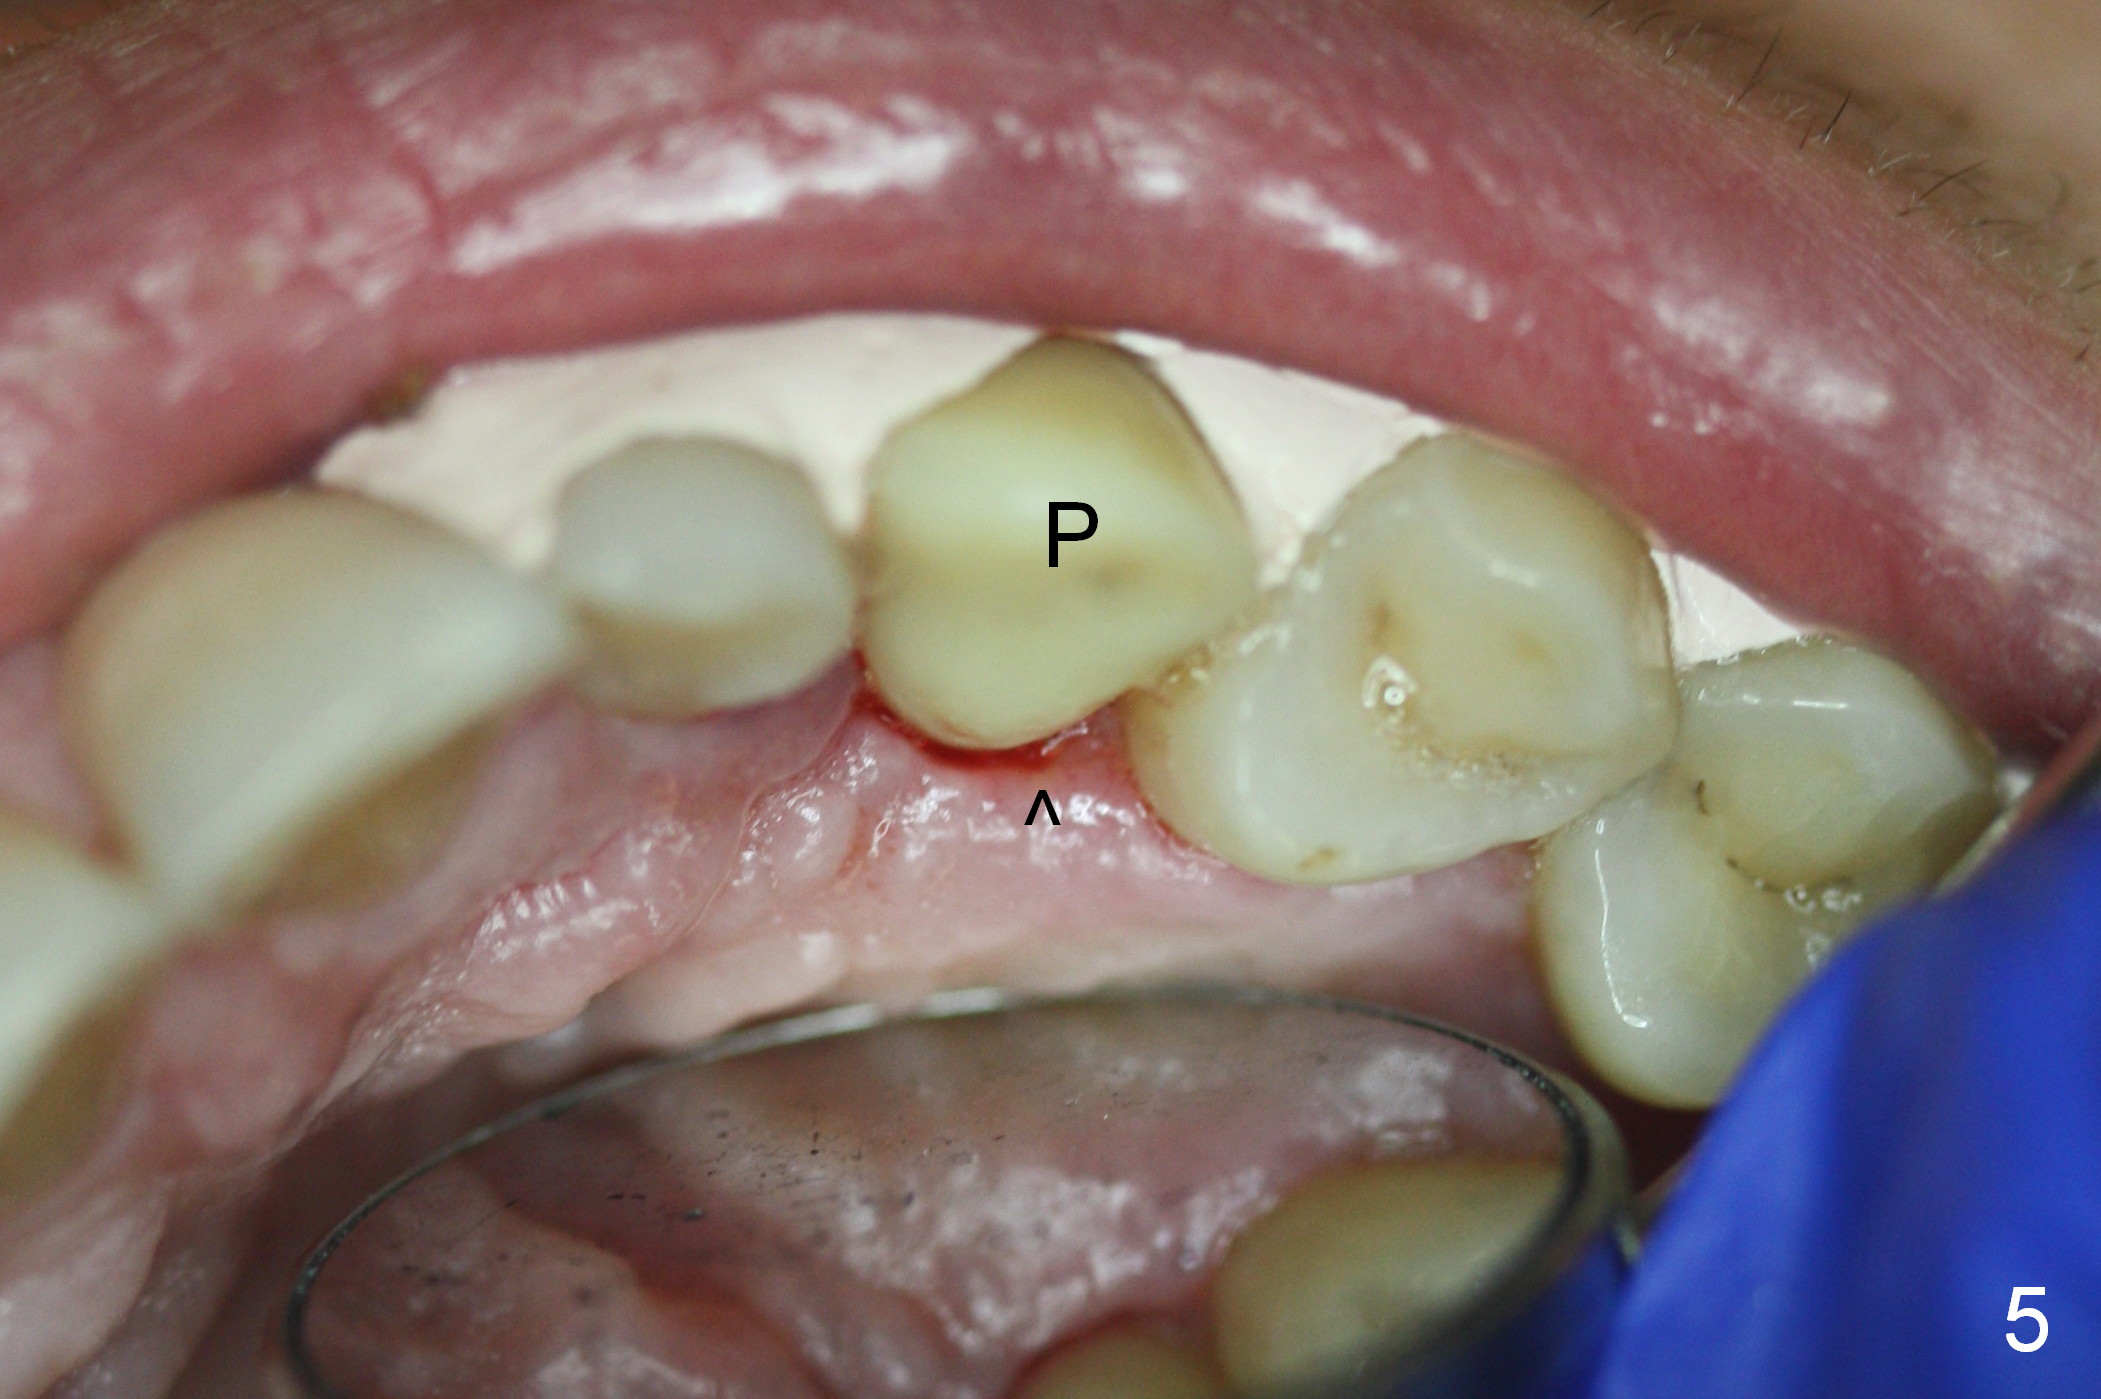

Six days postop, the patient is doing fine without nasal symptoms. Nasal speculum exam does not reveal apparent nasal floor perforation. The perio dressing remains around the provisional (Fig.4,5 P). Local scaling is provided for slightly tender palatal gingiva between the provisional and the neighboring tooth (Fig.5 ^). Continuous Chlorhexidine rinse is recommended.